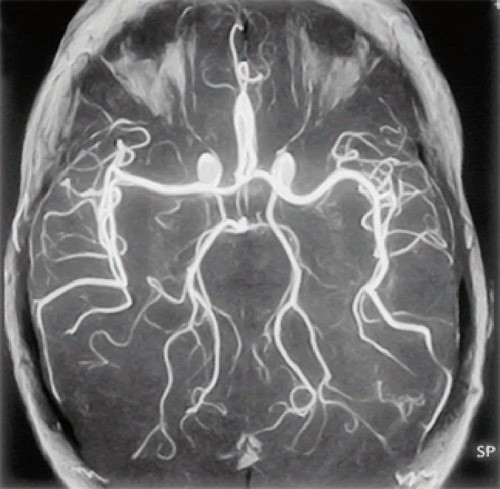

Что показывает МРТ сосудов головного мозга? С ее помощью послойно изучается состояние органа, а минимальная толщина срезов в 3–4,5 мм позволяет увидеть малейшие изменения в его структуре. Современное оборудование выдает не только плоские, но и трехмерные изображения исследуемого отдела. Кроме того, во время диагностики можно получить максимально точные снимки мягких тканей, не затемненных костными образованиями черепа.

Что покажет томограмма в ангиорежиме? С ее помощью врач оценивает состояние кровеносных сосудов в головном мозге и области шеи. Обследование помогает выявить причины головных болей, локализацию артериальных стенозов, сосудистых мальформаций и аневризм. С его помощью на ранних стадиях диагностируют инсульты и другие серьезные болезни мозга.

МРТ головного мозга и сосудов головного мозга позволяет получить трехмерную картину всей системы кровообращения головы. Она показывает тончайшие срезы сосудистых стенок и позволяет на ранних стадиях выявить тромбоз вен и другие серьезные сосудистые патологии. Диагностику назначают при: